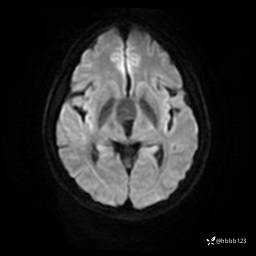

ADC: